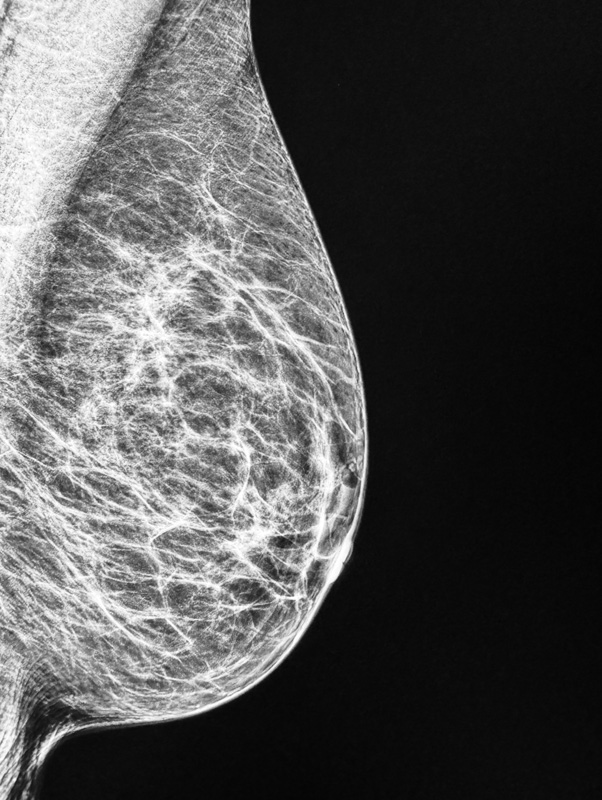

Mammographie / Tomosynthese

Die Mammographie ist die Röntgenaufnahme speziell für die Brust. Bei dieser Untersuchung zur Früherkennung und Diagnose von Brustkrebs setzen wir hochmoderne, digitale Geräte ein. Dabei machen unsere Mammographiebilder bereits kleinste Kalkablagerungen sichtbar und bieten damit wertvolle Anhaltspunkte für eine frühzeitige Therapie.

Die Tomosynthese:

Die Tomosynthese ist ein spezielles Röntgenverfahren der Brust. Hierbei wird die Brust in einzelnen Schichten, ähnlich einer CT-Untersuchung dargestellt. Dadurch können kleinere Tumore insbesondere bei dichten Drüsenkörpern besser und eher dargestellt werden. Die Tomosynthese bedeutet also mehr Sicherheit für Sie als Patientin.